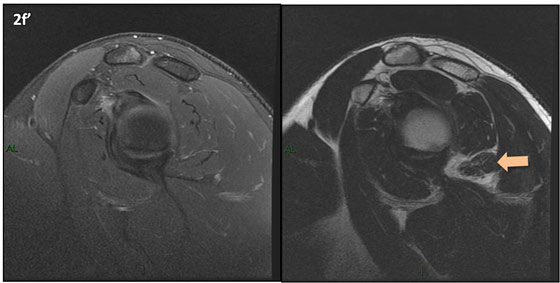

Figura 2 (a-j)': Imagens consecutivas de RM no plano sagital nas ponderaçõesT2 com supressão de gordura (DP SG) à esquerda e T2 à direita. Clique na seta para passar as imagens.

Figuras 2b a 2j’: Acompanhando o tendão do redondo menor (seta amarela fina) é possível notar lipossubstituição ao redor da junção miotendínea (setas amarelas grossas) e a atrofia principalmente da porção mais lateral (seta salmão). A porção mais medial (seta branca) tem volume preservado.

Repare que estas alterações também não são evidentes nas imagens com supressão de gordura no plano sagital.

Chafik et al. também relataram a presença de um pequeno nervo motor acessório em número variável que se insere na porção lateral do músculo redondo menor. O nervo acessório, ao contrário do principal, tem um curso reto e extra-fascial, sendo menos vulnerável aos efeitos compressivos. De fato, nos casos da atrofia parcial do redondo menor, é mais frequente a atrofia da porção mediodorsal com preservação da porção lateroventral, o que poderia ser explicada pela presença do ramo acessório mais lateral do nervo axilar, embora atrofia isolada do componente lateroventral tenha sido reportada em cerca de 17% dos casos de atrofia de apenas uma porção, o que pode ter sido causada por lesão do nervo acessório. No caso do paciente deste mês, a atrofia é mais evidente nesta porção mais lateral e ventral do redondo menor.

É importante que o protocolo de ressonância magnética do ombro tenha sequências ponderadas em T1, T2 ou densidade protônica (DP) sem supressão de gordura em pelo menos dois planos, idealmente nos planos coronal e sagital, para a detecção de lipossubstituição que pode passar despercebida nas imagens com supressão de gordura.